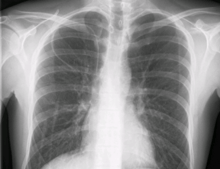

During subclavian vein central line placement, the catheter can be accidentally pushed into the internal jugular vein on the same side instead of the superior vena cava. A chest x-ray is performed after insertion to rule out this possibility.[18] The tip of the catheter can also be misdirected into the contralateral (opposite side) subclavian vein in the neck, rather than into the superior vena cava.

The line is then inserted using the Seldinger technique: a blunt guidewire is passed through the needle, then the needle is removed. A dilating device may be passed over the guidewire to expand the tract. Finally, the central line itself is then passed over the guidewire, which is then removed. All the lumens of the line are aspirated (to ensure that they are all positioned inside the vein) and flushed with either saline or heparin.[1] A chest X-ray may be performed afterwards to confirm that the line is positioned inside the superior vena cava and no pneumothorax was caused inadvertently; electromagnetic tracking can be used to verify tip placement and provide guidance during insertion, obviating the need for the X-ray afterwards.